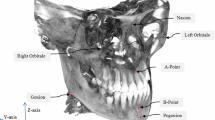

Nowadays, with the increased diffusion of Cone Beam Computerized Tomography (CBCT) scanners in dental and maxillo-facial practice, 3D cephalometric analysis is emerging. Maxillofacial surgeons and dentists make wide use of cephalometric analysis in diagnosis, surgery and treatment planning. Accuracy and repeatability of the manual approach, the most common approach in clinical practice, are limited by intra- and inter-subject variability in landmark identification. So, we propose a computer-aided landmark annotation approach that estimates the three-dimensional (3D) positions of 21 selected landmarks.

The procedure involves an adaptive cluster-based segmentation of bone tissues followed by an intensity-based registration of an annotated reference volume onto a patient Cone Beam CT (CBCT) head volume. The outcomes of the annotation process are presented to the clinician as a 3D surface of the patient skull with the estimate landmark displayed on it. Moreover, each landmark is centered into a spherical confidence region that can help the clinician in a subsequent manual refinement of the annotation. The algorithm was validated onto 18 CBCT images.

Automatic segmentation shows a high accuracy level with no significant difference between automatically and manually determined threshold values. The overall median value of the localization error was equal to 1.99 mm with an interquartile range (IQR) of 1.22–2.89 mm.

The obtained results are promising, segmentation was proved to be very robust and the achieved accuracy level in landmark annotation was acceptable for most of landmarks and comparable with other available methods.